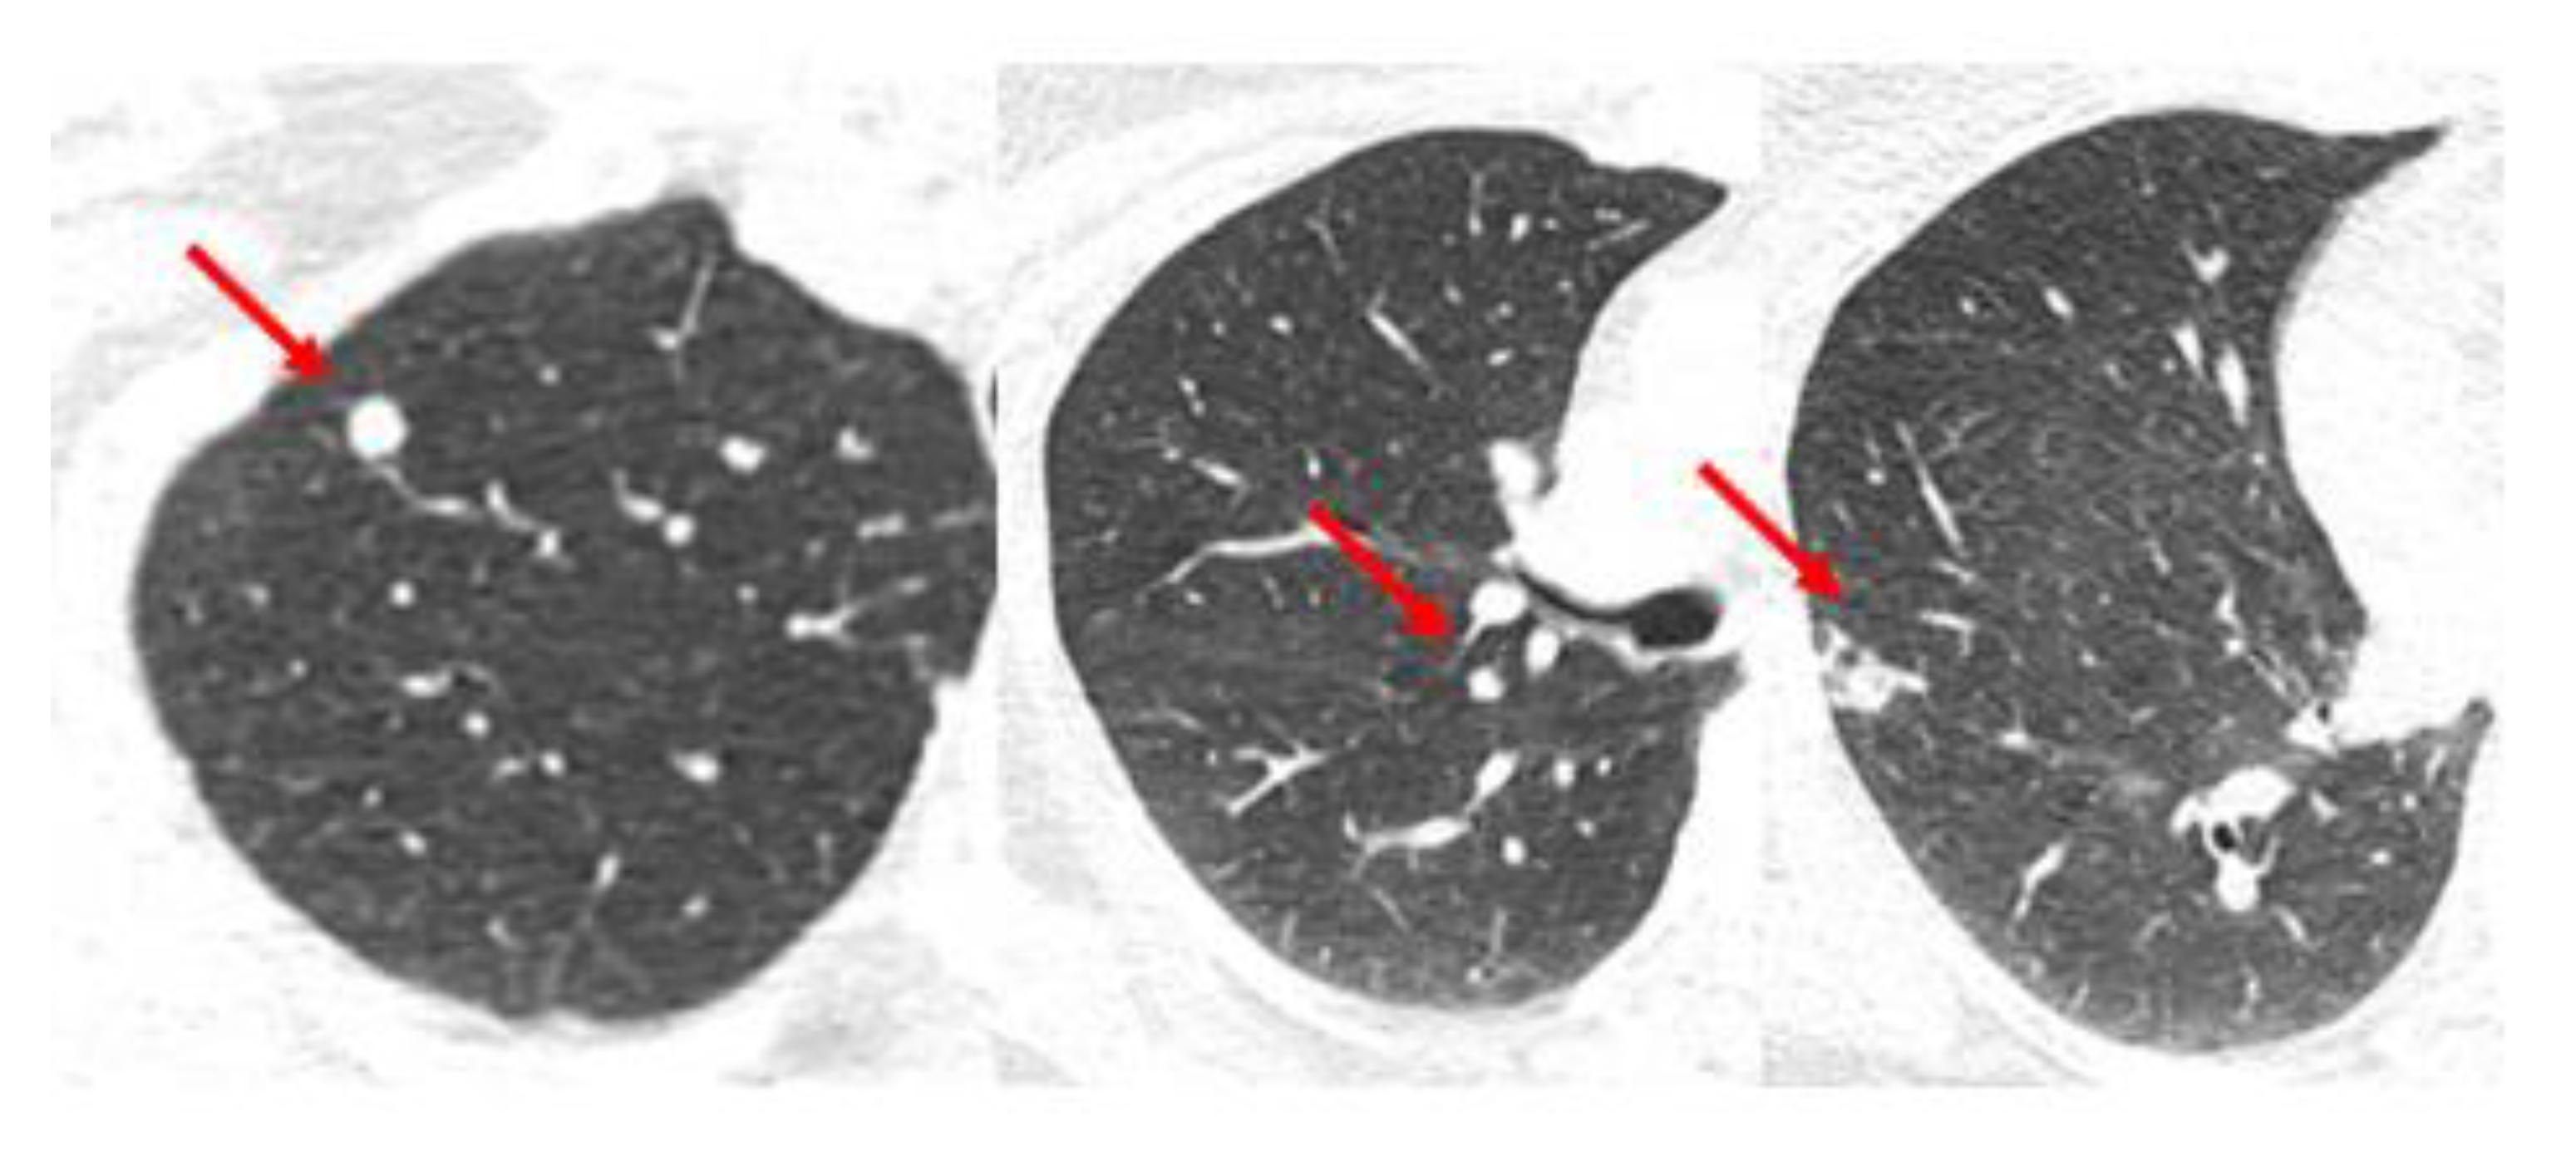

Figure 2. Case 1: Simultaneous oligometastases. A 60-year-old woman presents with a locally advanced cancer of the left breast cT1N3M1 with an oligometastasis of the sternum. The sternal oligometastasis is shown on representative images from CT (a) and bone scan (b) imaging. (c) Radiation therapy to the left breast and sternum. The left image shows a colorwash image superimposed on a radiation planning CT of the dose from the sternum-directed SBRT given 40 Gy in 5 fractions, and the right image shows the colorwash of the dose of 50 Gy given to the breast and regional nodes combined with the sternal treatment. The yellow color indicates the prescribed dose of radiation, and the green and blue colors around the edges indicate the medium and lower dose fall-off of the radiation dose plan (d) The appearance on a CT scan image of the sternum 3 years after treatment. There is minimal residual sclerosis of the sternum with no evidence of progression.